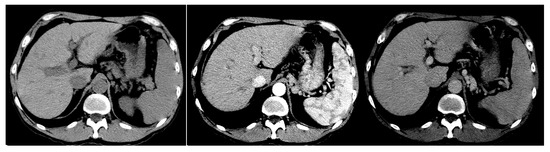

| Scan Phase | CT Scan Timing | Contrast Agent Diffusion |

|---|---|---|

| N Phase: Non-contrast Phase | <0 s | No contrast agent injected |

| A Phase: Arterial Phase | 25 s | Contrast agent diffused into hepatic arterial vessels |

| V Phase: Venous Phase | 60 s | Contrast agent refluxed into hepatic venous vessels |

| P Phase: Equilibrium Phase | 120 s | Contrast agent diffused into hepatic capillary tissues |